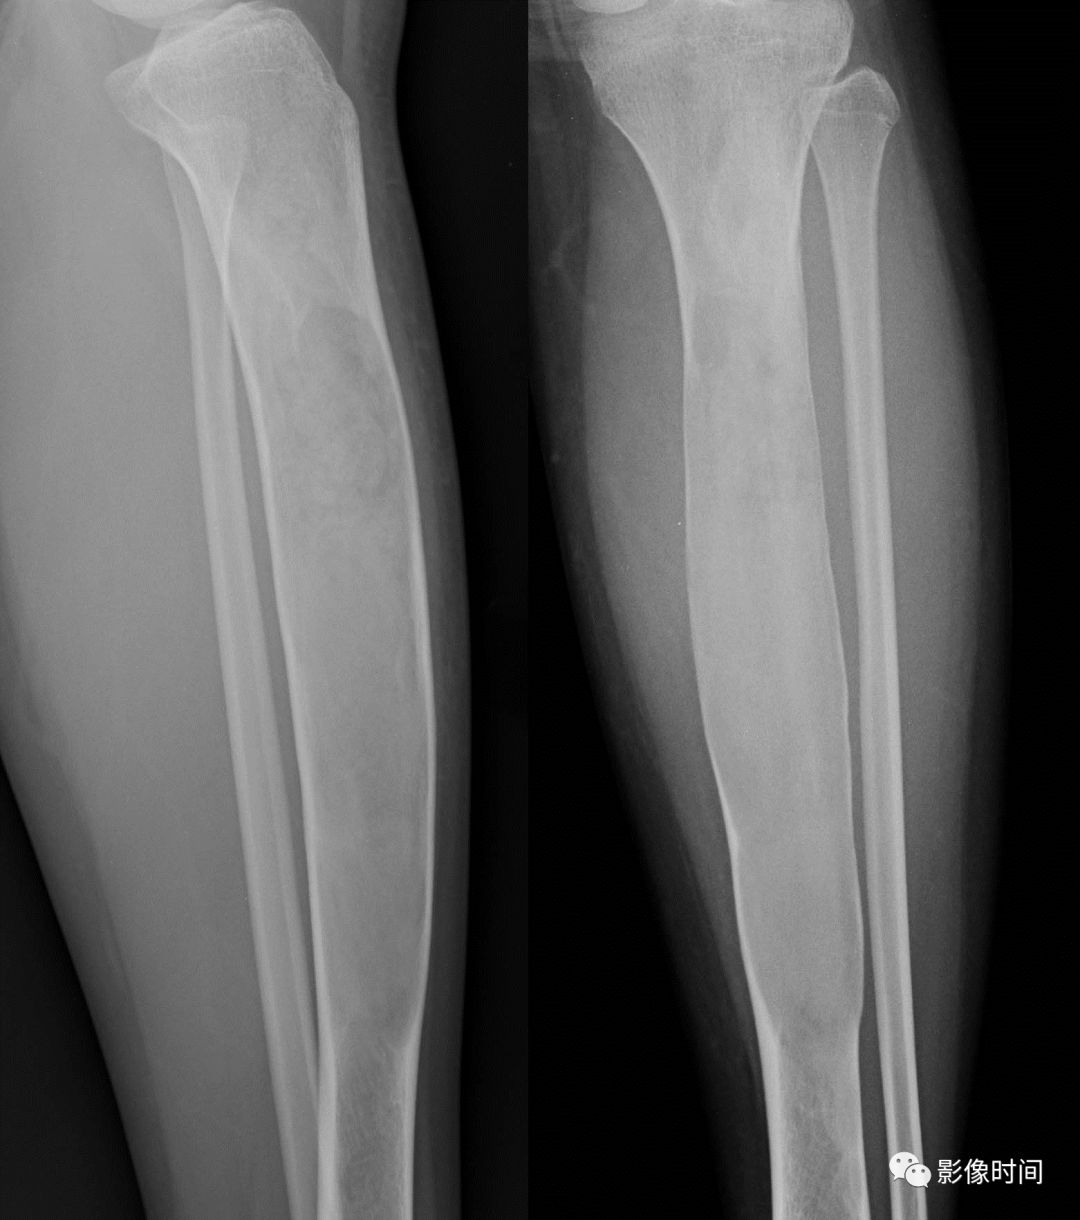

(二)膨胀性破坏  膨胀性破坏是地图样破坏的特殊形式,影像学表现为骨质破坏区骨膨胀,周围可见不同程度扩张的骨壳(图 5、图 6、图 7、图 8)。

膨胀性破坏是由于肿瘤从骨皮质内面破坏,骨外膜增生形成新生骨造成膨胀的。

引起膨胀性破坏见于大多数良性肿瘤和肿瘤样病变如单纯性骨囊肿,动脉瘤样骨囊肿、内生软骨瘤和软骨粘液纤维瘤等,少数也可见于恶性肿瘤如转移瘤、骨髓瘤等。

图 8  膨胀性破坏:软骨粘液样纤维瘤